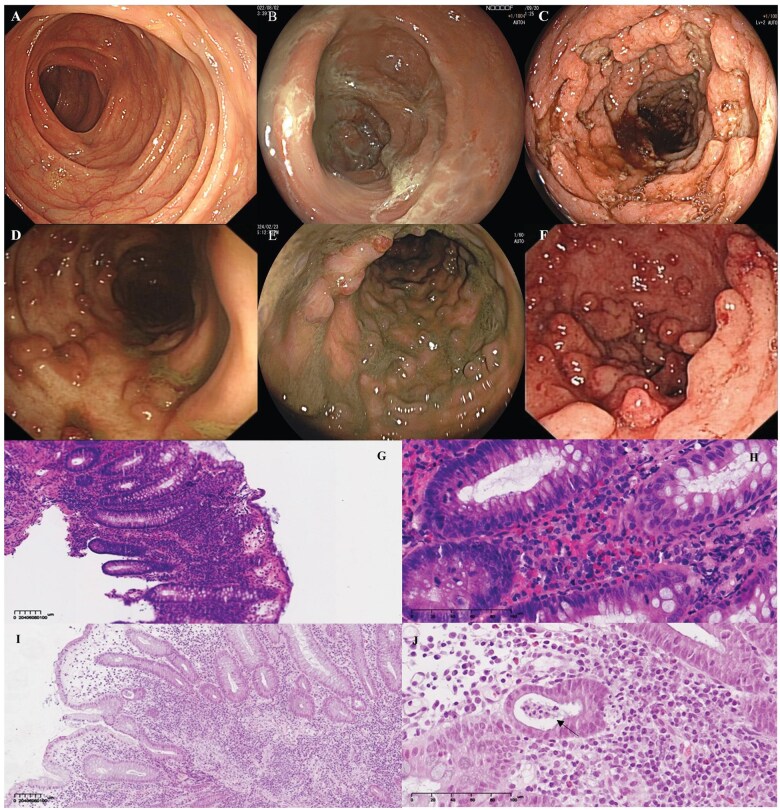

A case of ulcerative colitis progression after ileostomy reversal following rectal cancer surgery.

直肠癌手术后回肠造口逆转后溃疡性结肠炎进展1例。